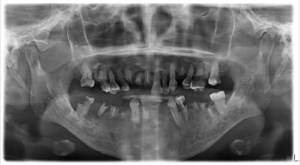

某天小美因牙痛及不能張口的問題而來就診,經臨床檢查及X光顯示,原來是下顎的阻生智慧齒作怪。因口腔空間不足,智慧齒不能順利長出。由於清潔難度增加,除了會導致牙肉發炎之外,也會引致前面大牙的局部牙周病及蛀牙問題。